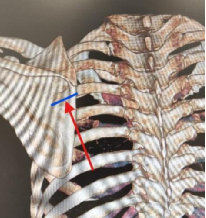

因其右侧第4、第5后肋骨折断端错位较重、错位骨折部分重叠、患者疼痛较重(见图一、图二);考虑其术后生活需求,错位的肋骨需要较好的复位,在和患者充分沟通后,制定了肋骨骨折内固定手术治疗。

图一 图二